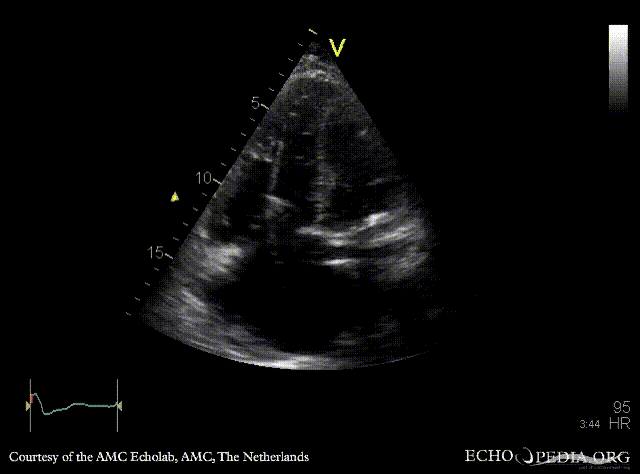

| A4CH: dilated right ventricle and right atrium, pacemaker lead in situ